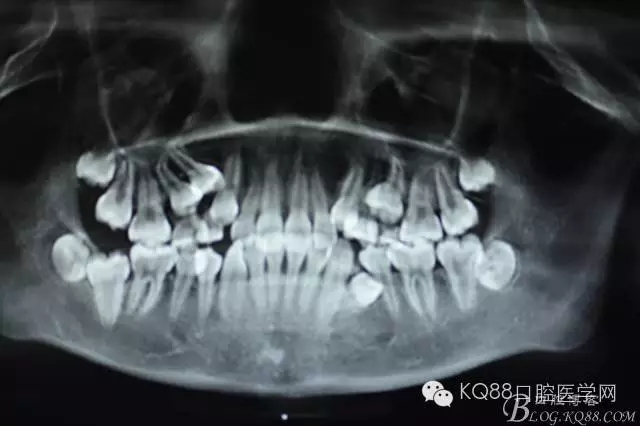

圖2.術(shù)前cbct檢查:54、55乳牙滯留,14、15埋伏阻生,14位于15的上方。

圖3.全景片檢查:14位于15與13之間,正畸科要求拔除14,難度可想而知。54、55滯留。